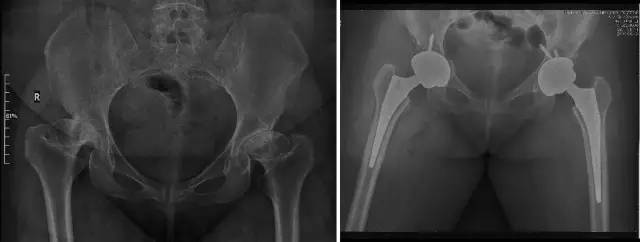

各种晚期骨关节病的关节置换手术治疗是北京清华长庚医院关节外科中心的一大特色,包括股骨头坏死、髋膝骨关节炎、类风湿关节炎、强直性脊柱炎、髋关节发育不良、关节强直、超过80岁的超高龄股骨颈骨折患者的关节置换手术等,我中心在人工关节初次置换及翻修上作了大量工作,置换的难度和手术效果方面已达到国际先进水平,导航下全膝关节置换术:大大提高膝关节置换手术的精确度。

股骨头缺血性坏死

髋关节发育不良

强直性脊柱炎双髋强直

股骨颈骨折